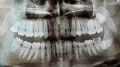

У меня два нижних зуба мудрости выросли неправильно, т.е. горизонтально, вылезли не полностью, а частично торчат. Один уже с кариесом и даже откололся.

Стоит ли удалить два нижних ретенированных зуба мудрости одновременно?

Вообще, рекомендуется удалять ретенированные 8-е зубы по одному (максимум по два), так как это довольно длительная и сложная манипуляция. Пациенту сложно просидеть так долго с широко открытым ртом.

Таким образом, моё мнение, лучше удалять по одному, причём с перерывом в несколько недель, если зубы не беспокоят.